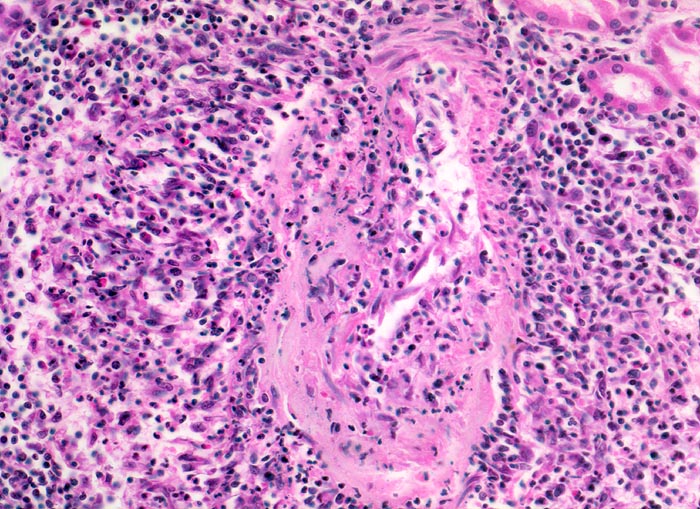

Polyarteritis nodosa Makroform: akute Phase

Mittelgrosse Arterie mit einer nicht ganz frischen fast zirkulären Gefässwandnekrose. Nur ein kleiner Gefässwandabschnitt lässt noch eine Muskelschicht erkennen. Entsprechend der fast zirkulären Nekrose ist das ganze Gefäss mantelförmig umgeben von einem gemischten Entzündungsinfiltrat (neutrophile und eosinophile Granulozyten, Lymphozyten, Plasmazellen und Histiozyten). Stellenweise greift das Entzündungsinfiltrat auch auf die Gefässwand über.

Makroskopischer Befund der Nieren: Vergrösserte Nieren mit Petechien und mehreren frischen, teils hämorrhagischen Infarkten.